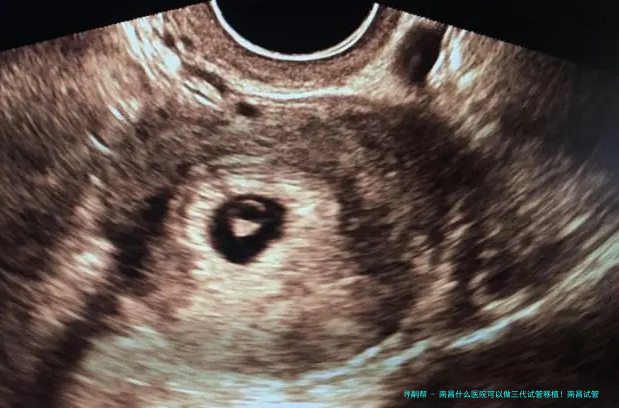

三代试管移植技术是辅助生殖技术中的先进手段,主要用于解决精子健康状况差、卵子质量问题以及遗传性疾病等方面的生育难题。 通过严格的胚胎检查筛选和遗传检测,可以提高成功率,同时减少因遗传不足导致的子孙健康风险。 三代试管移植技术的使用为许许多多家庭提供了生育希望。